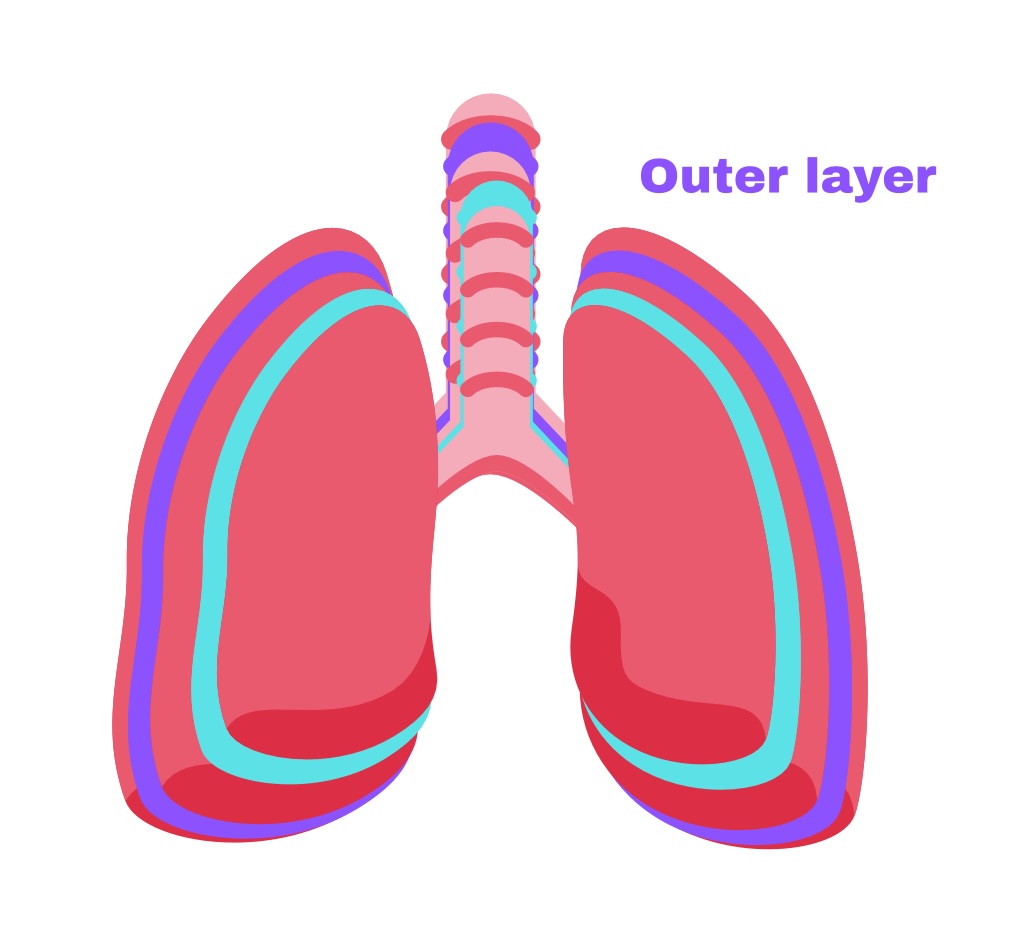

Partial pleura

Outer layer